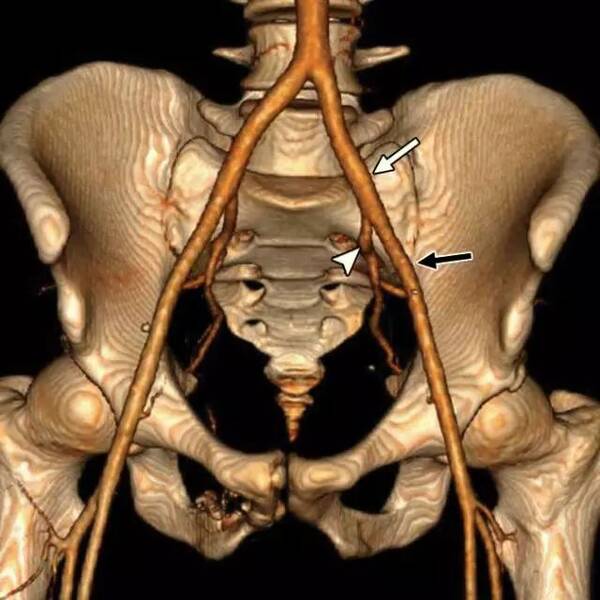

右髋臼镙钉旁在阴影

右髋臼镙钉旁在阴影

600x450 - 22KB - JPEG